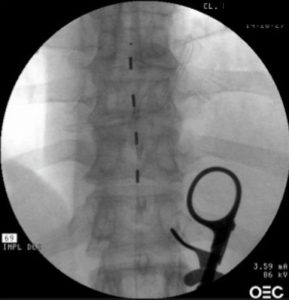

Contraste Radiológico injectado na articulação facetada C1 / C2 esquerda, gravemente lesada pela artrite reumatóide.